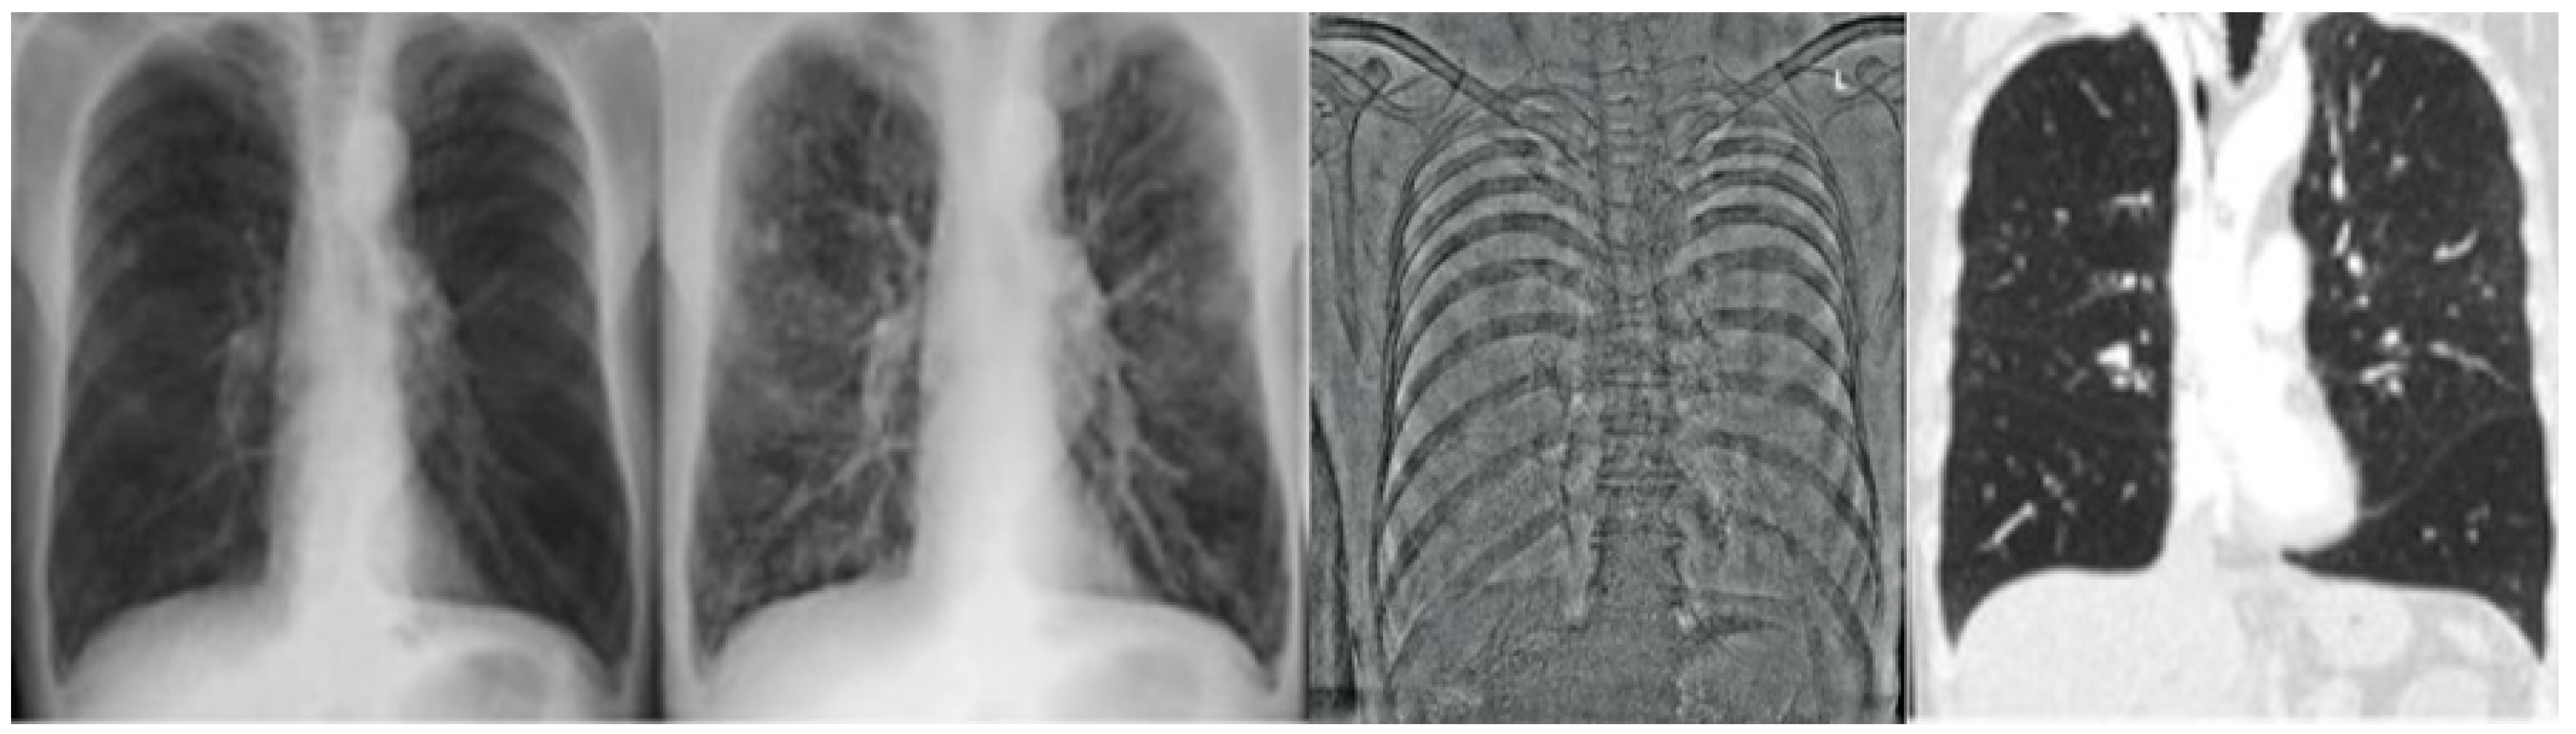

2.2.1. CR and DE Images

2.2.2. CT Images